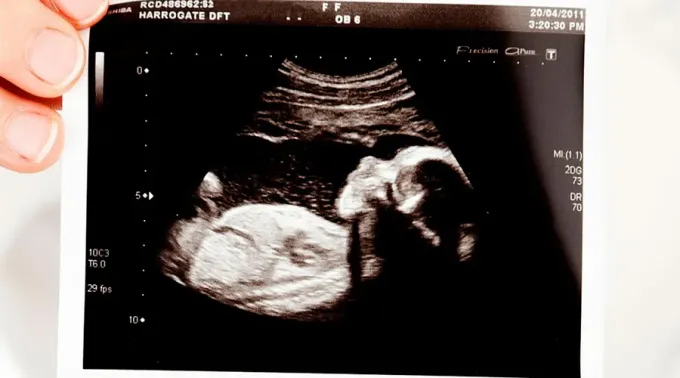

"As mulheres grávidas terão a oportunidade de ver seu próprio bebê e ouvir os batimentos cardíacos", afirmou o Pro-Life Utah em um vídeo promocional da iniciativa.

Segundo o grupo, as estatísticas mostram que “até 80% das mulheres que desejam fazer um aborto passam por uma mudança de opinião e optam por ficar com o bebê quando veem a ultrassonografia”.

"A mentira do grupo de células' é revelada, e as mulheres que veem seu ultrassom podem perceber que é um bebê".

Em seu site, o grupo pró-vida declarou que a "Clínica de ultrassom móvel Pregnancy Choice Utah" ficará localizada do lado de fora da clínica de aborto Planned Parenthood Metro, em Salt Lake City. Os serviços serão oferecidos por "médicos formados e capacitados em atendimento ao cliente".

A “clínica móvel rosa brilhante” oferecerá às mulheres testes de gravidez gratuitos, exames de ultrassom e opções de aconselhamento sobre a gravidez, a educação dos filhos e os recursos de adoção.